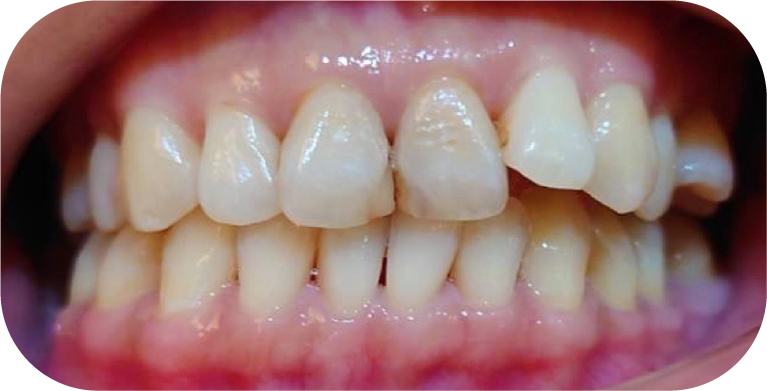

全口重建

牙齒矯正

隱適美

人工植牙